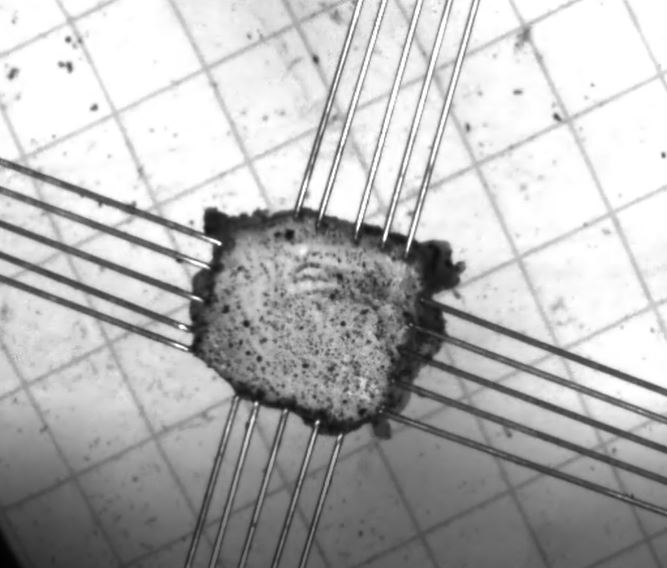

The question of meningeal tissues anisotropy is complex and should not be limited to the comparison of uni-axial tests in various directions. Bi-axial mechanical testing enables quasi-static characterization in conditions closer to physiological context while requiring development of specific testing system as well as specific post-processing analysis. Combined to microscopy to provide an identification of the meningeal micro-structure, this study aims at identifying mechanical characteristics under bi-axial loading conditions of extracted swine pia mater (PM) and dura and arachnoid complex (DAC).